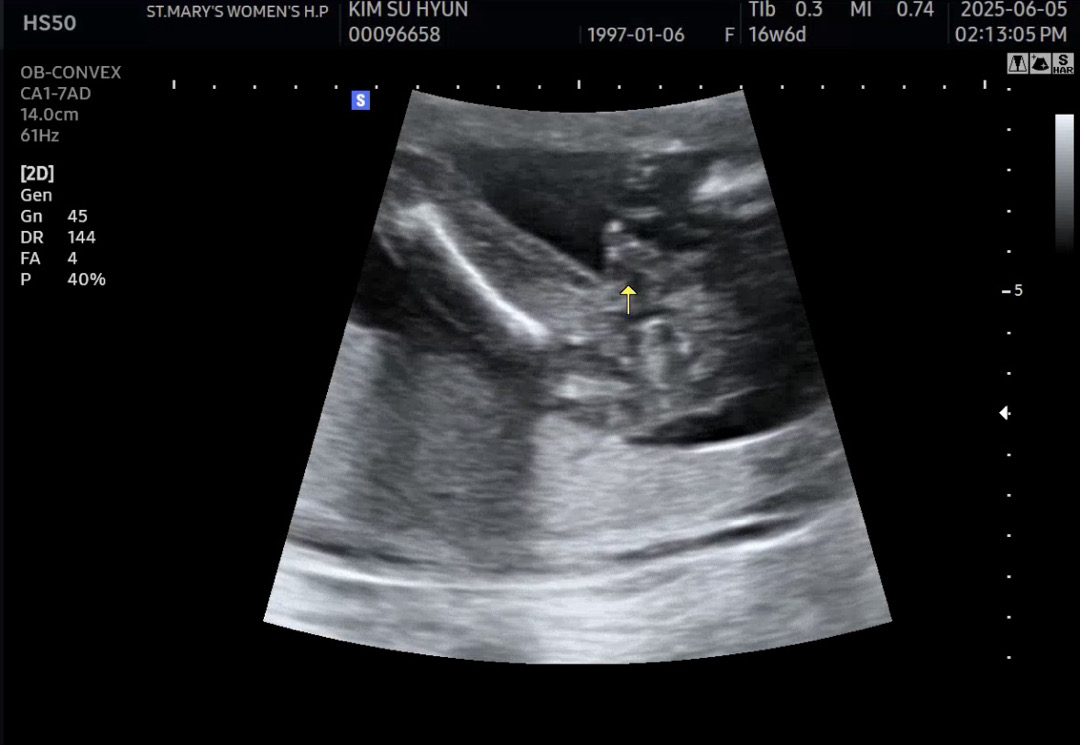

남자아이 맞겠죠??

90프로가 아들이라고 하셨는데 화살표부분 이거 생식기 맞죠??? 있던게 갑자기 없어지진 않겠죠 ㅎㅎ

저정도로 튀어나온거면 아들 맞는거 같아요 ㅋㅋㅋ 제뱃속 친구도 저렇게 튀어나와있어요 ㅋㅋ